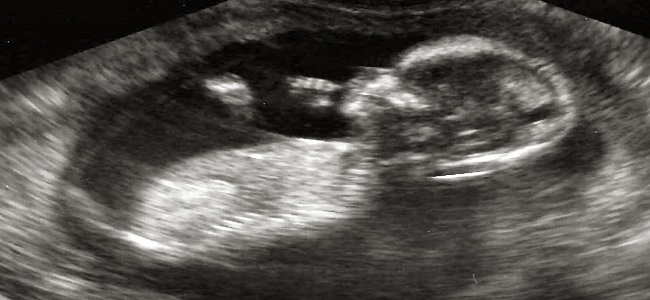

W 14 tygodniu ciąży oczy i uszy dziecka znajdują się już na właściwym miejscu. Na twarzy zaczynają rosnąć brwi i włosy. Całe ciało malucha jest pokryte licznymi zakończeniami nerwowymi, dlatego jest bardzo wrażliwe. Kobieta jeszcze nie odczuwa, kiedy dziecko się porusza. Ruch to teraz jego ulubione zajęcie. Wystarczy położyć rękę na brzuchu ciężarnej, aby dziecko przybliżyło się do niej. Jedynie czubek głowy dziecka nie jest wrażliwy na dotyk. Dzięki temu poród nie jest aż tak bolesny dla maleństwa. Teraz dziecko waży 25 gram i ma około10 cm.